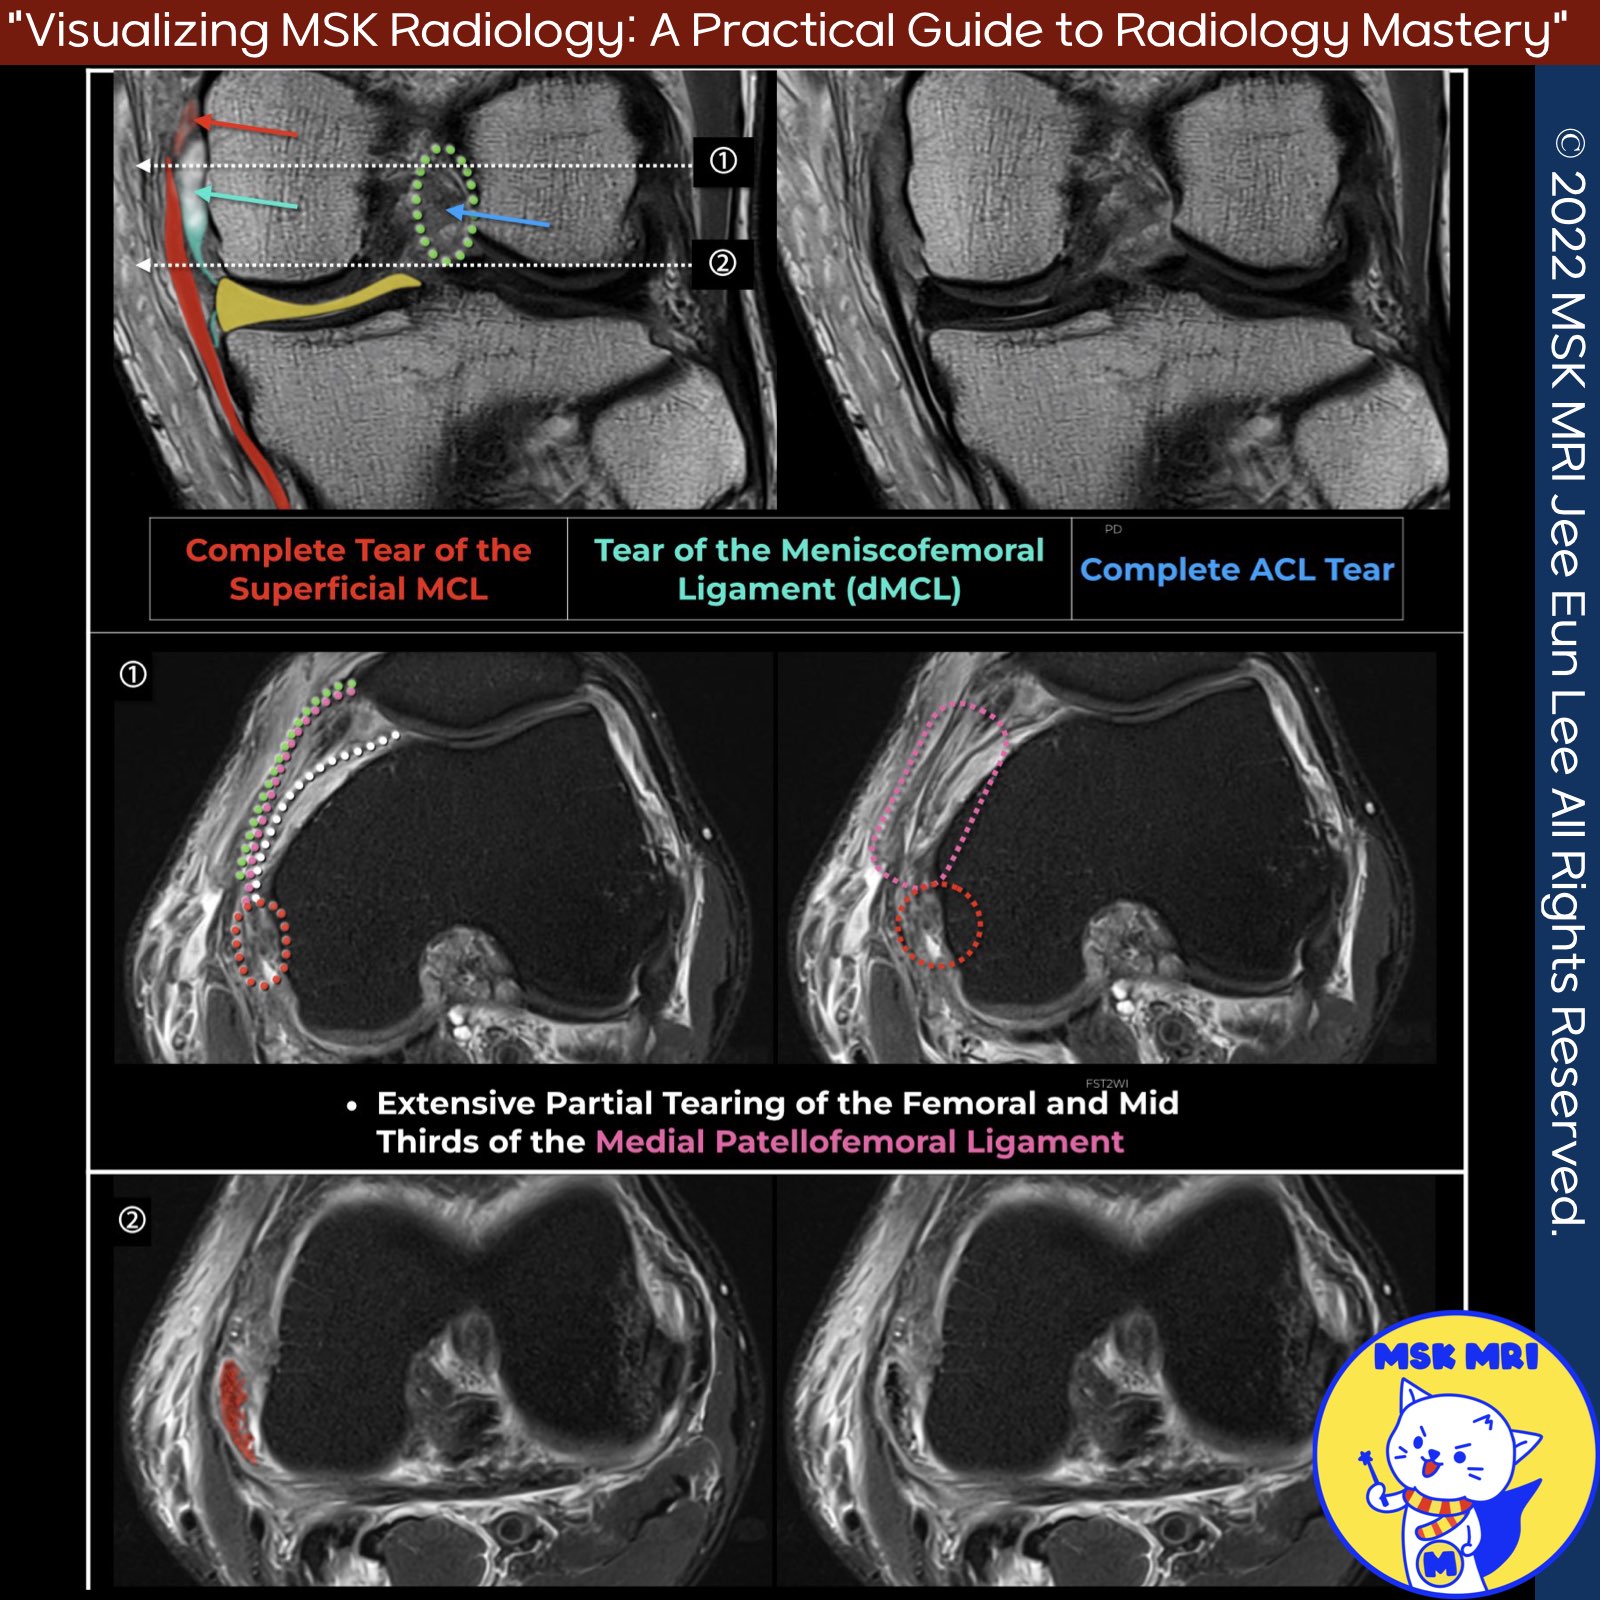

📌 MRI Findings in Grade 3 Superficial MCL Injury

- Complete discontinuity of the proximal superficial MCL and adjacent soft tissue edema, indicating a full-thickness tear.

📌 Involvement of MPFL in MCL Injuries

- Injuries of the superficial MCL can propagate anteriorly to involve the anterior MPFL.

- The MPFL merges with the fibers of the MCL at the epicondyle.

- The MPFL appears abnormal in most patients with clinically and MRI-documented cases of superficial MCL sprains or tears at or above the knee joint line.

✅ Clinical Relevance of MPFL Abnormalities

- The femoral third of the oblique decussation component of the MPFL, which arises from the anterior margin of the upper superficial MCL, appears abnormal in approximately 90% of cases involving superficial MCL injuries.

- Despite these MPFL abnormalities, there is no evidence of concurrent lateral patellar dislocation on the initial MRI scans.

✅ MPFL Anatomy

- The MPFL consists of a thinner, more superior transverse component attaching to the medial femoral condyle and a broader, more inferior oblique decussation component arising from the upper segment of the superficial MCL.